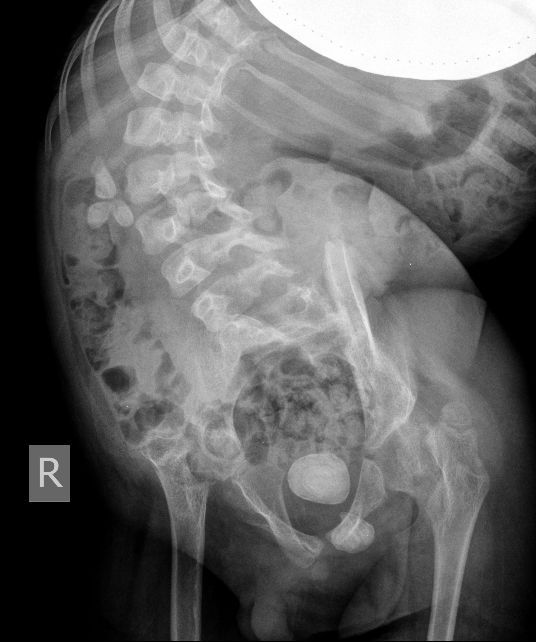

Для того, чтобы продемонстрировать степень ортопедических проблем и облегчить задание (или усложнить :) ) добавляю обзорную рентгенограмму брюшной полости

Поскольку откликов нет, добавляю экскреторные урограммы этого же пациента

Нейрогенный мочевой пузырь (?), МКБ, конкремент мочевого пузыря, двухсторонний мегауретер, конкремент правой почки.

Всё верно, только что вот это ?

И что законтрастировалось на экскреторных урограммах около мочевого пузыря?

Если честно, и я изначально не совсем понял, где находится конкремент (а это конечно же конкремент), локализованный на урограммах. При первичном исследовании на УЗИ его я не видел (либо он спрятался за тенью конкремента мочевого пузыря, либо я обрадовался редкой находке конкремента такого размера в мочевом пузыре - 2.5 см, и не посмотрел что ниже). Тем не менее при ретроспективном анализе архивированных сонограмм, как мне кажется, он попал в один из сканов, м.б. не совсем чётко.

И всё -же, где конкремент :?:

Возможно, в дивертикуле либо в нижней трети мочеточника..

Верификация:

Выдержка из протокола операции- "...вскрыт мочевой пузырь, обнаружен камень 4 х 3х 2.5 см, плотный, удалён. При дальнейшей ревизии мочевого пузыря обнаружен вколоченный камень в шейке мочевого пузыря и в уретре, удалён камень 2 х 1.5 х 1.5 см. При осмотре устья левого мочеточника - последний зияет, мочеточник расширен до 1 см, учитывая расширение мочеточника, проведена антирефлюксная пластика по Грегуару..."